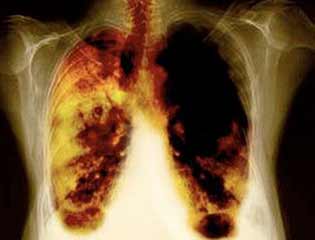

Восстановление легких: Через несколько месяцев после отказа от курения легкие начинают восстанавливаться. Уменьшается количество кашля и хрипов, а также улучшается функция легких. Через 1-2 года риск развития заболеваний легких, таких как хронический бронхит, значительно снижается.

- Спустя 1-9 месяцев исчезают кашель и одышка: реснички, которые помогают очищать легкие, начинают функционировать нормально, что снижает риск инфекций.

Отказ от курения значительно снижает риск развития различных заболеваний, таких как рак легких, сердечно-сосудистые заболевания и хронические обструктивные болезни легких. Через 1-2 года после прекращения курения риск сердечно-сосудистых заболеваний может снизиться до уровня некурящего человека, а через 10 лет риск развития рака легких уменьшается на 50% по сравнению с курящими.